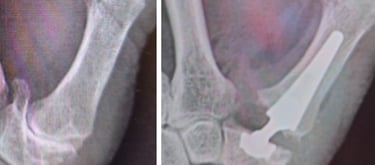

Rizartrosis

Artrosis de muñeca

Artrosis